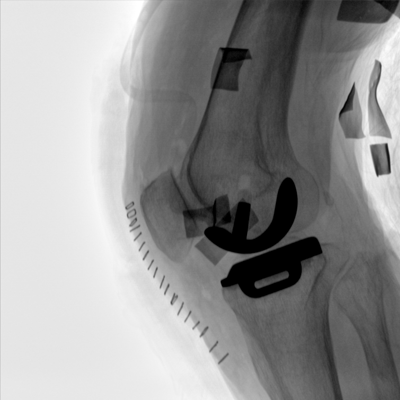

大尺寸動態(tài)平板探測器,高DQE、低噪聲、圖像清晰。采用多分辨率圖像增強處理技術(shù),不同部位不同圖像處理算法,滿足客戶多樣化的需求。

采用智能變頻脈沖透視技術(shù),優(yōu)化圖像質(zhì)量的同時降低輻射劑量,呵護醫(yī)患健康

多角度自由旋轉(zhuǎn),滿足患者復(fù)雜擺位需求。